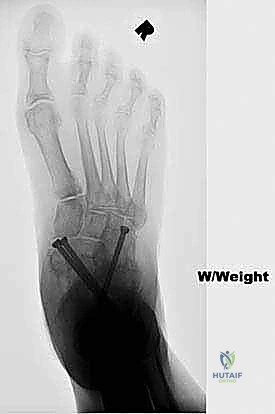

FIG 3 • Radiographs of a 56-year-old diabetic woman with severe pes planovalgus deformity and gross subluxation of the subtalar and transverse tarsal joints radiographically.

Standard weight-bearing radiographs of both the foot and ankle are critical in evaluating severe pes planovalgus deformities. The foot films will determine the amount of subluxation or dislocation of the subtalar and transverse tarsal joints that must be corrected. They can also determine whether there is deformity or bone loss that demands the addition of structural bone grafts. The ankle radiographs are required to confirm that the severe heel valgus is isolated to the hindfoot. Occasionally, severe valgus hindfoot deformity leads to increasing deltoid ligament incompetence, creating a valgus tilt of the talus within the ankle mortise. Deltoid ligament incompetence and valgus tilt of the ankle may necessitate surgical correction of the ankle as well should hindfoot realignment with triple arthrodesis fail to rebalance the tibiotalar joint ( FIG 3 ).

- All talonavicular and subtalar joints healed ( FIG 4 ).

Radiographic Correction Was Comparable To Previous Series Describing Traditional Two-Incision Triple Arthrodesis.

In a cadaver study, 90% of the calcaneocuboid joint articular surface was able to be prepared successfully from the medial incision.

- Two of the 17 patients (12%) developed a nonunion of the calcaneocuboid joint. Neither of these was symptomatic.

Seventeen patients underwent single-medial-incision triple arthrodesis.

All 17 demonstrated clinical improvement in alignment and pain relief.

FIG 4 • After single-medial-incision triple arthrodesis, the patient shown in Figure 3 had excellent correction of her deformity without wound-healing complications.

B